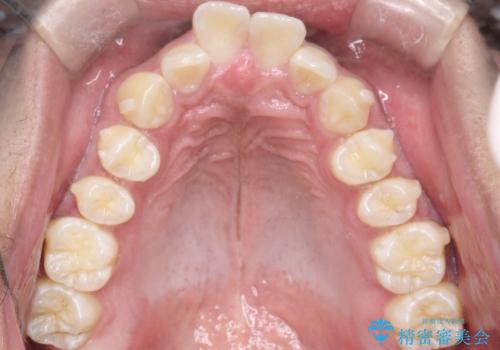

インビザラインによる出っ歯の矯正

- 出っ歯と下の歯のガタガタを主訴に来院されました。

上の奥歯を後方に移動させて、スペースを作り前歯を内側に引っ込める計画としました。

インビザラインによるマウスピース矯正で治療をすることとしました。

インビザラインをしっかり使用していただいたので、スムーズに治療をおえることができました。